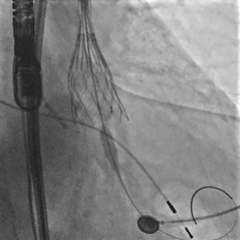

预先置入8mm球囊,准备撤出大鞘

髂外动脉可见造影剂渗出,8mm球囊进行阻断

植入覆膜支架,造影可见轻微出血

植入第二条覆膜支架,无造影剂渗出,手术结束